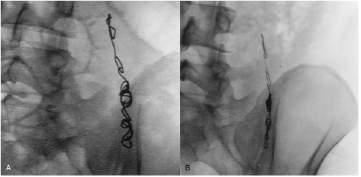

Barrett et al [66] demonstrated similar results for W MDS coils used for endovascular embolisation of varicoceles in the scrotum, presenting radiographic evidence of W resorption in 4 out of 18 patients (figure 3), and elevated W blood levels in 18 out of 19 patients (mean 40 months post-implantation). Bachthaler et al [60] reported W coil corrosion for intracerebral aneurysms and dural fistulae 26 months post-implantation in 9 out of 14 patients also by plain radiography, with two patients displaying complete coil resorption. W blood levels were elevated in 6 out of 14 patients, and urine levels were elevated in all. Others have reported similar radiographic and blood serum results with the use of W embolisation coils in intracranial aneurysms, abdominal aortic stent grafts, spermatic vein varioceles, oesophageal and gastric varices, and other pathological blood vessels (figures 4 and 5) [61, 67–70].

Figure 3. Endovascular embolisation of varicoceles in the spermatic vein with W coils. (A) Image obtained during procedure; (B) 57 months later, with clear reduction in the substance, thickness, and overall volume of the coil [66].